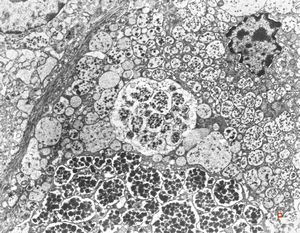

oral saprophytic bacterium